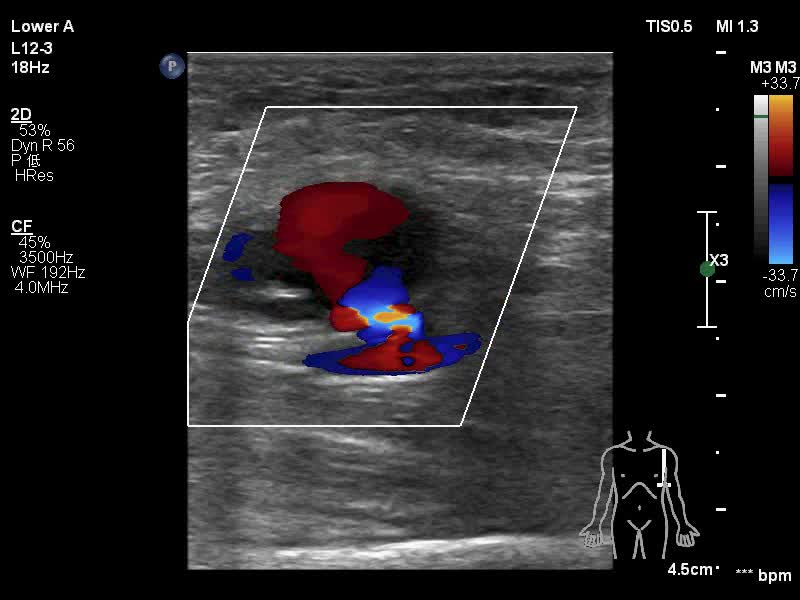

左侧腋动脉及近心段肱动脉无异常,于远心端近肘窝上方处可见肱动脉管壁连续性中断,断口约0.27cm,其旁一液性无回声区,CDFI检查可见红蓝交替彩色信号显示,断口处彩色信号斑斓,PW采集可见双向高速血流频谱,蓝色为肱动脉血流进入液性区,呈搏动性,PSV达2m/s ↓

相比静态图,动态图来的更加直观,供站友加深印象 ↓